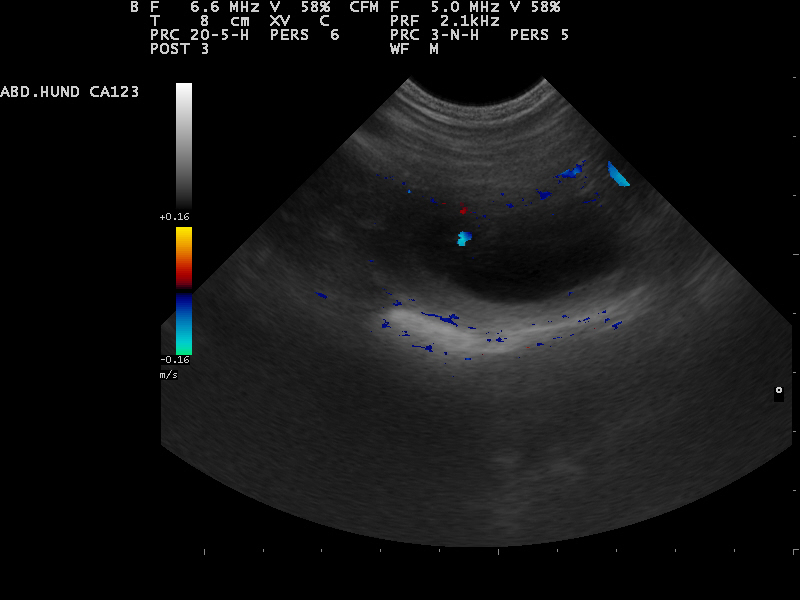

Am 22. Tag sind die Embryonen sichtbar. Der Herzschlag kann zur Diagnose der Trächtigkeit herangezogen werden. Anstrengende Aktivitäten sind

15.12.2015 jetzt zu vermeiden.Die Proteinzufuhr im Futter kann erhöht werden. Hierfür eignet sich sehr gut die Gabe von Welpenfutter. Zu diesem Zeitpunkt kann

mit einer Ultraschalluntersuchung der Zustand der Trächtigkeit festgestellt werden. Besprechen Sie mögliche Risiken einer solchen Untersuchung mit dem Tierarzt.

22.12.2015 Dies ist der beste Zeitpunkt, um die Trächtigkeit anhand des Herzschlags zu diagnostizieren.

Die Embroynen sind etwas walnussgroß und sind gleichmäßig im Uterus verteilt.

Die Ultraschall-Untersuchung hat ergeben das Alexa trächtig ist und wir gespannt auf

unseren B-Wurf warten können

Das sind die ersten Bilder unseres B-Wurfes